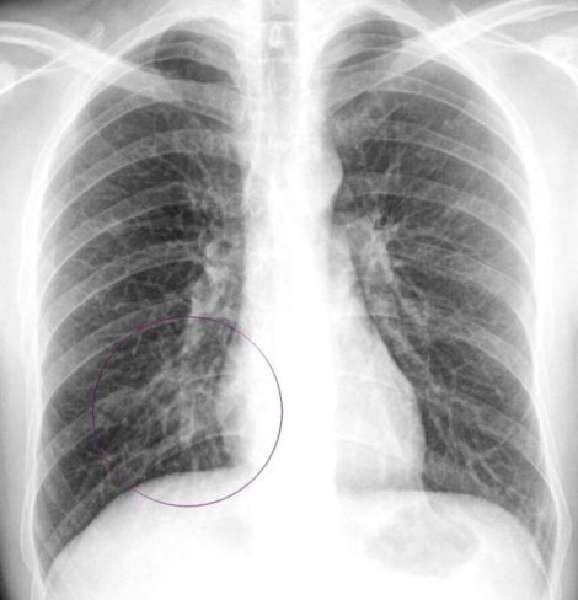

Рентгенография

Основным способом диагностики этих заболеваний, понятным всем врачам, является рентгенологическое обследование. У врача не будет и сомнения в определении диагноза, когда он изучит снимок.

Бронхит проявляется явным рисунком бронхиального дерева. На снимке будут видны даже маленькие разветвления бронхов, которые при нормальном состоянии никогда не проявляются.

Пневмонию можно определить по затемненным участкам легких на снимке. Эти участки могут быть разными по размерам – это зависит от степени поражения сегментов и долей легких.